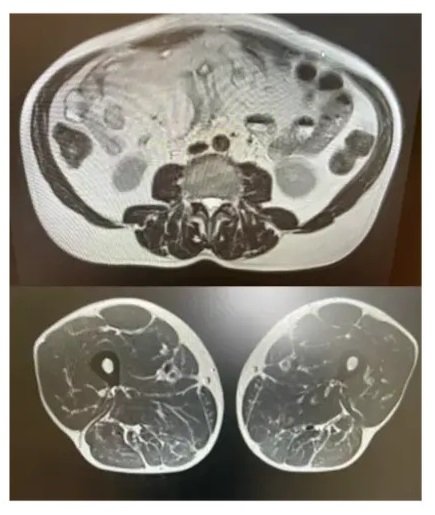

Figure 1

Figure one illustrates an MRI of human abdominal visceral fat. Visceral fat is a silent killer–most people are unaware of its existence. Furthermore, many physicians overlook this crucial health factor as well. A plethora of research exists detailing the dangers of visceral fat; however, our disease exploiting systems don't allow for its awareness to be promoted. This research can be found across Google on various public sources and libraries, including the Mayo Clinic and the National Institute of Health. It is important that you understand how deadly it is for yourself. Instead, my website is intended for the educated consumer already aware of the profound dangers of visceral fat and desires to obtain optimal health, as well as the best life possible by eradicating visceral fat.

Visceral fat resides deep inside your abdomen; it appears white in the MRI image on the bottom and painted red in the top image (See Figure 1). Subcutaneous fat is colored yellow in the cross-sectional view on top. How much visceral fat you have is most accurately established by safe MRI without radiation but can also be seen in an abdominal CT (See last image below especially if you have ever had an Abdominal CT to find out how much visceral fat you have at least when the scan was done - so keep reading - I cover a few scans showing just how much disease in the body correlates to visceral fat that most people have NO idea about).